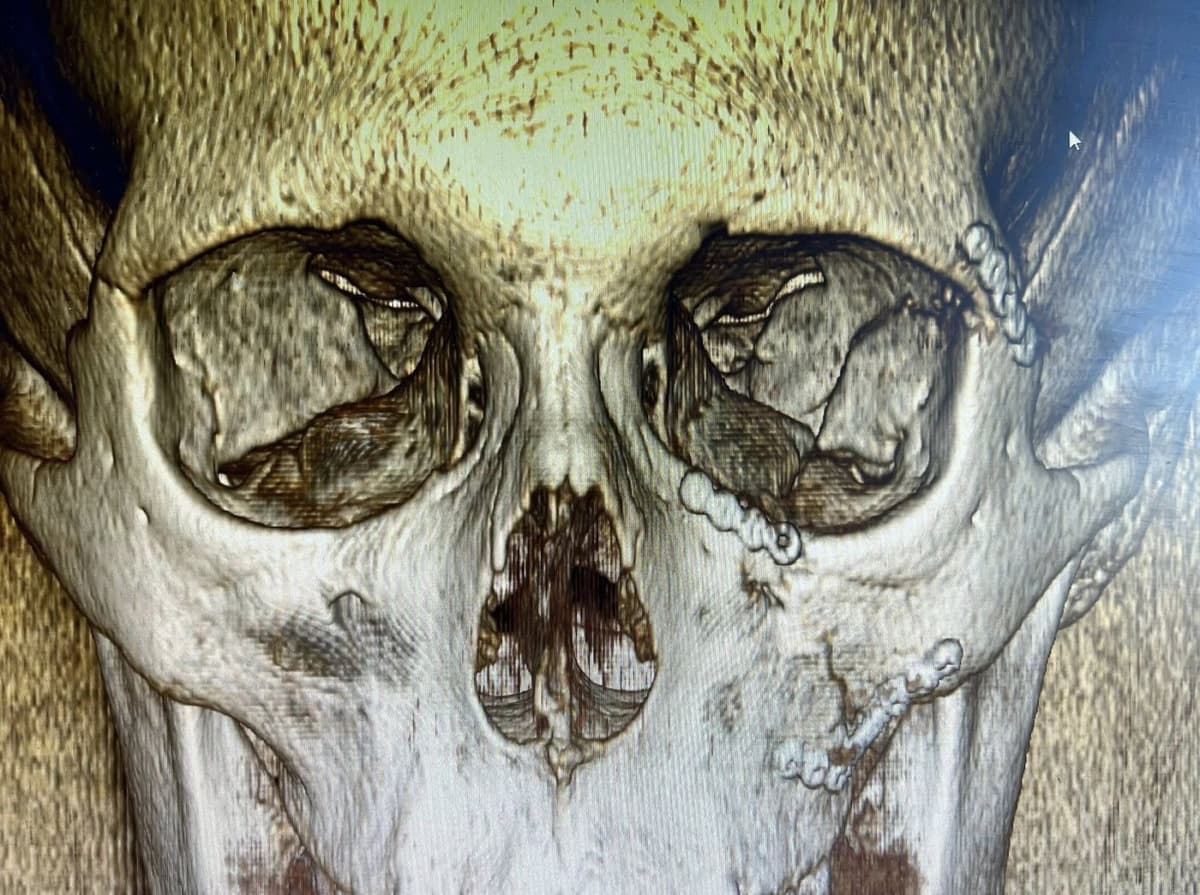

14-річний хлопчик потрапив до Закарпатської обласної дитячої лікарні після сильного удару. У нього діагностували відкритий перелом виличної та верхньощелепної кісток зі зміщенням вилично-орбітального комплексу.

Лікарі провели складну операцію відкриту репозицію перелому з фіксацією уламків титановими пластинами, залучивши для цього провідного щелепно-лицевого хірурга.